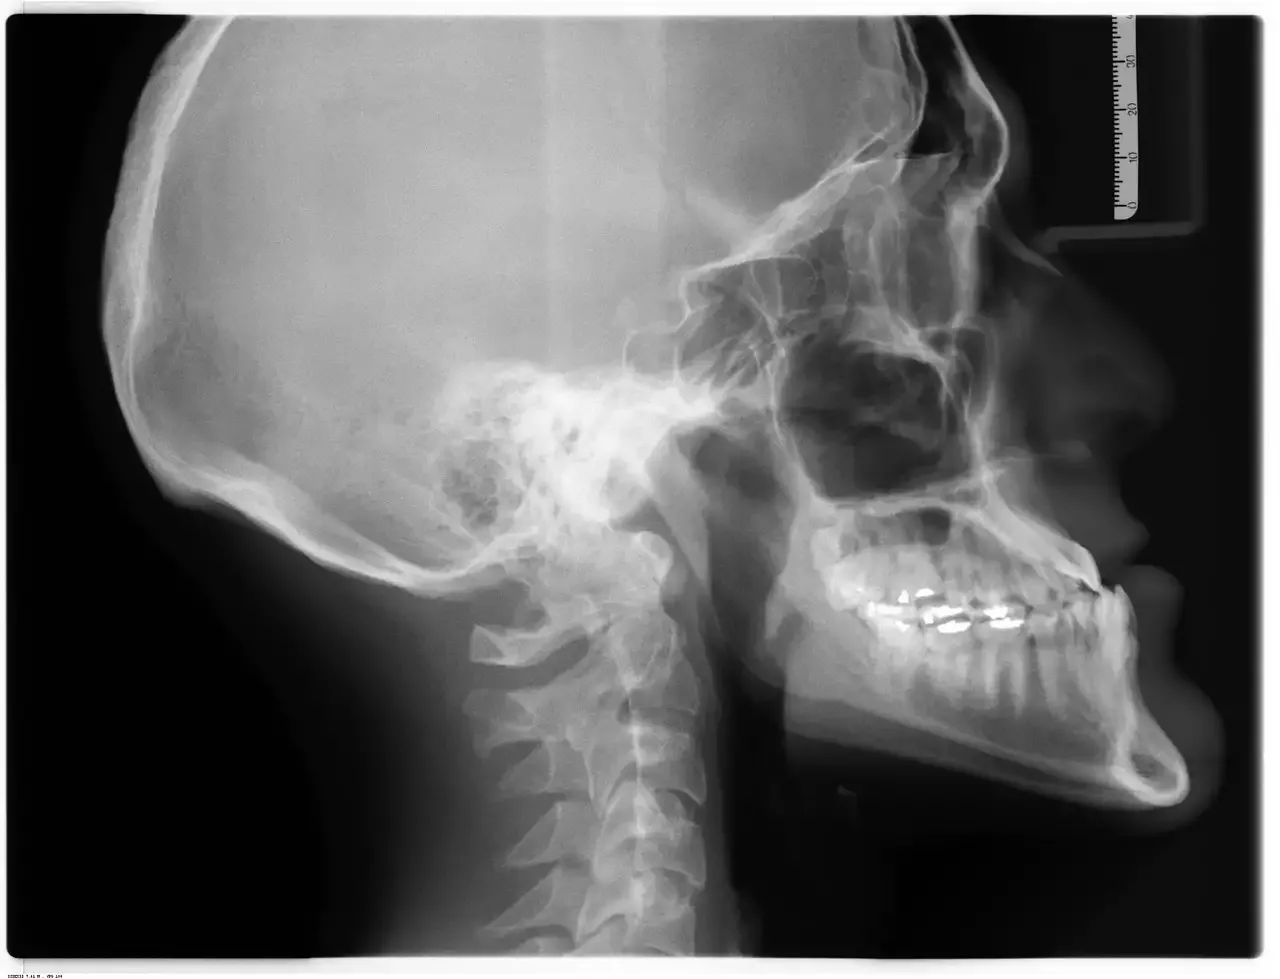

ניתוח אף, המכונה גם ניתוח אף, הוא אחד מההליכים הנפוצים ביותר המבוצעים על ידי מנתחים קוסמטיים. אף על פי שהאף הוא תכונת פנים קטנה, היא…

ניתוח לעיצוב מחדש של הלסת כדי להגדיר את הפנים שלך